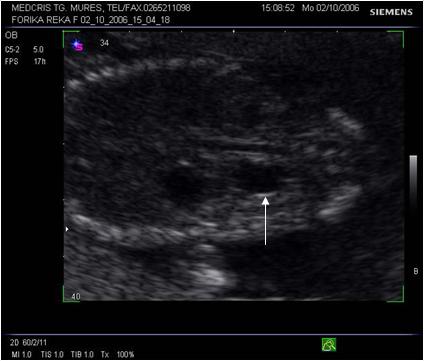

Fig. nr. 273. Dilatatie pielocaliceala renala fetala, unilaterala, la 16 sapt.( sageata)